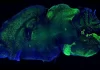

The new AAVs can cross the blood-brain barrier, which typically keeps many drugs from getting into the brain. The engineered AAV capsids also accumulate much less in the liver than AAV9, potentially reducing the risk of liver side effects that have been seen in other AAV9-based gene therapies. This family of AAVs, called the PAL family, could be a safer and more efficient way to deliver gene therapies to the brain.

Stanton and colleagues focused on pinning down AAVs that cross the blood-brain barrier. They turned to a method developed in the Sabeti lab called DELIVER, in which scientists generate millions of capsids and look for AAVs that successfully deliver their payload to certain target cells. Using DELIVER, the team developed the PAL family of AAVs that cross the blood-brain barrier more effectively than AAV9—the only FDA-approved viral vector for use in the nervous system.

They found that the PAL AAVs were three times more effective at producing therapeutic mRNA in the macaque brain compared to AAV9.

The team also found that the engineered viruses had a unique pull to the brain. PAL-treated macaques had one-fourth of the viral material in their livers as AAV9-treated primates did, suggesting that the new capsids could help limit the liver toxicity of other gene therapies.